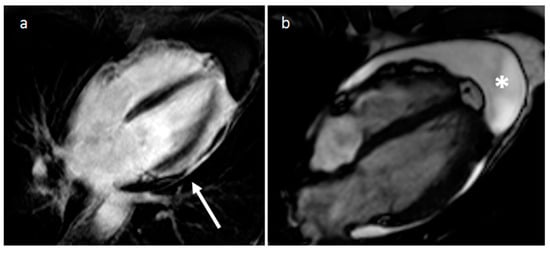

3.1. Thrombus

| Thrombus | Adulthood | LA, LAA (AF) LV (MI) | Asymptomatic, embolic events | Non-enhancing Intracardiac lesion | Acute: Low echodensity, rounded with smooth contours Chronic: High echodensity, linear or crescentic lesions along the endocardial surface | Low attenuation, no contrast enhancement, chronic thrombus may be calcified Usefulness of delayed CT imaging, as in the LAA stasis of blood can simulate a thrombus on early arterial images | Acute: hyper T1w and T2w Subacute: hyper T1w and hypo T2w Chronic: low T1w and T2w No enhancement. |